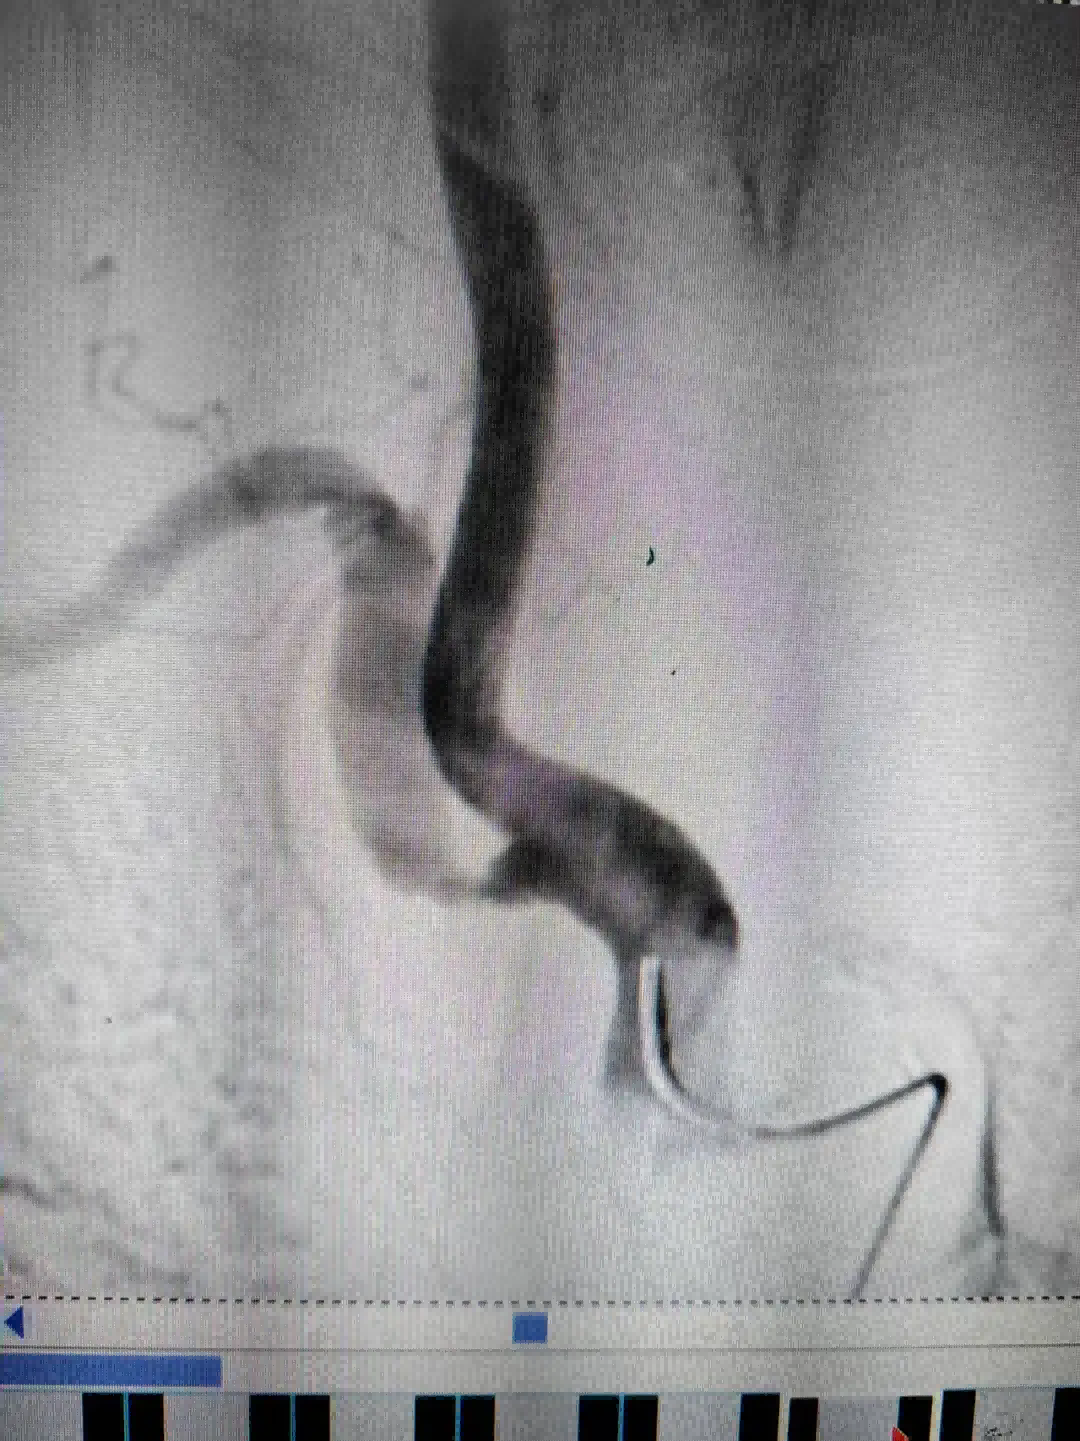

为进一步明确病情,12月23日,医生为王阿姨进行了脑血管造影检查。结果提示,其右侧锁骨下动脉狭窄程度较两年前明显加重,手术指征明确。经与家属充分沟通并取得同意后,神经内科团队随即为王阿姨施行了右侧锁骨下动脉支架植入术。手术顺利,术后造影显示血管狭窄段已被成功扩开,血流恢复通畅。

术前与术后对比术后,王阿姨的头晕症状得到显著改善,生活质量大幅提升。出院前,她特意将一面锦旗送至神经内科:“谢谢你们帮我解决了这么多年头晕的老毛病,现在整个人都轻松了!”。